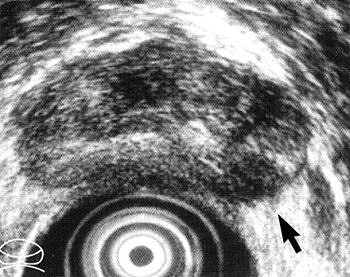

| Transverse transrectal ultrasound scan of prostate in 59-year-old man with prostate cancer shows hypoechoic lesion (arrow) in left posterior peripheral zone. Irregular or spiculated margin along the capsule is evidence of ECE of tumor. Focal ECE was confirmed at surgical pathologic examination. Figure 2. Hricak H, Choyke PL, Eberhardt SC, et al. "Imaging Prostate Cancer: A Multidisciplinary Perspective," Radiology 2007;243:28-53. |